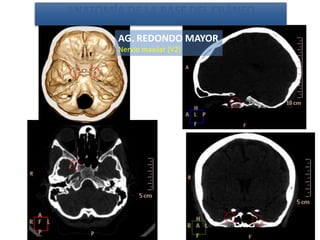

AG. REDONDO MAYOR

Nervio maxilar (V2)

Estudio 2

• Estudio sin y con contraste, con reconstrucciones sagitales y coronales

del estudio con contraste.

Se observa una lesión ocupante de espacio en lóbulo frontal derecho que

presenta un tamaño de 18 x 32 x 22 mm (cc x ap x tr), bilobulada, no del

todo bien delimitada, con realce en anillo irregular, con hipocaptación

central, probablemente por necrosis, y asociada a un extenso edema

vasogénico con efecto masa tanto sobre los surcos de la convexidad

como sobre la cisterna insular, el sistema ventricular y la línea media,

esta última con un desplazamiento de 5 mm a la altura del septo

interventricular.

No se aprecian otras lesiones focales intra o extraaxiales de significación

patológica.

Habría que considerar como primera posibilidad que se tratase de una

lesión metastásica, por bien un tumor primario, aunque no se puede

descartar otras opciones, sin imprescindible correlación con la clínica y

con sus antecedentes.